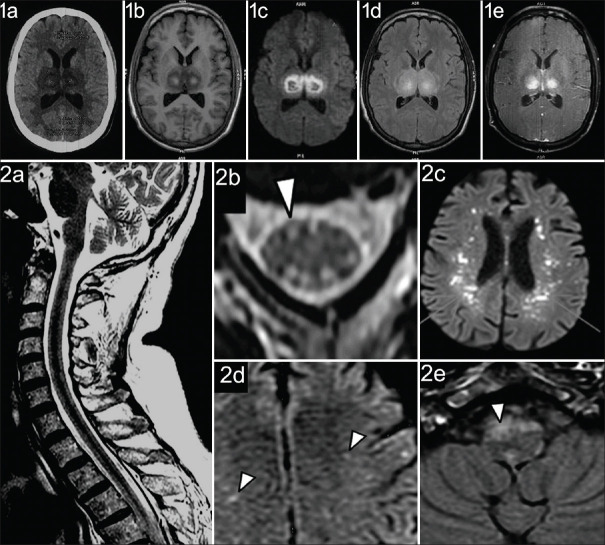

Abstract: Viral encephalitis is one of the leading presenting features of neurologic emergencies in tropical and subtropical areas. Chikungunya encephalitis (CE) and dengue encephalitis (DE) are important neurologic disorders of the central nervous system (CNS) with increased morbidity and mortality. This review discusses the pathogenesis, clinical features, diagnostic workup, and management of CE and DE, and provides insights into the vector-borne diseases with the help of literature obtained from clinical studies, reviews, and case series/reports. Chikungunya, as well as dengue viruses, are spread by the bite of Aedes aegypti and Aedes albopictus . The pathogenesis includes either direct invasion of the nervous system and/or immune-mediated CNS injury. It starts with fever, body aches/myalgia, and arthralgia (more in chikungunya) and may progress to encephalitis, if not treated properly during the initial stages. Laboratory investigations show leukopenia/thrombocytopenia, immunoglobulin M (serum and cerebrospinal fluid) positivity, and real-time polymerase chain reaction positivity. Brain imaging does not have any specific diagnostic clue. However, chikungunya has a predilection for the medulla oblongata, while dengue may affect the thalamus to show the classical double doughnut sign. Treatment is invariably medical, with adequate hydration and additional supportive care, although steroids and immunoglobulins have also been tried. CE and DE are critical vector-borne illnesses of CNS with guarded prognosis. The exact pathogenesis needs further research insights. A high index of clinical suspicion and aggressive management can lead to better outcomes. No specific therapy or immunization is available for CE or DE. However, these can be controlled by cleaning and eliminating all potential vector-breeding places.